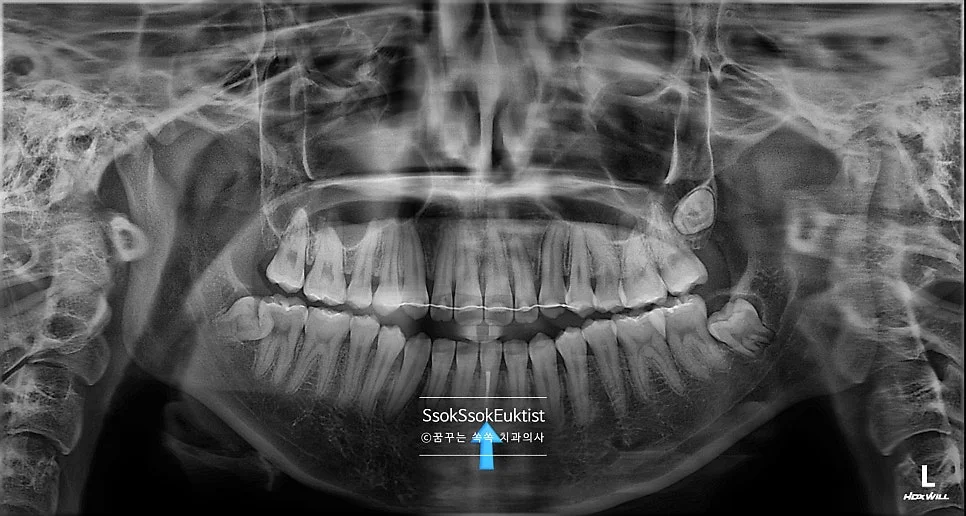

진단 X-ray — 다른 치아에 비해 신경관(검은 음영)이 매우 좁아져 있는 모습

해당 치아의 X-ray를 촬영해 보면 다른 치아들에 비해 신경관(검은 음영)이 매우 좁아져 있는 모습인데요.

신경 조직이 오랫동안 자극을 받으면서 자극에 대한 방어기제로 신경관이 좁아진 것입니다. 그간 얼마나 아팠을까요ㅜ

저렇게 좁아진 신경관의 치아를 신경치료하는 것은 매우 고난도입니다. 특히나 치아 중 가장 얇은 아래 가운데 앞니라면 더욱 어려운 신경치료인데요.

치아의 정중앙에 있는 신경관을 찾는 과정에 조금만 잘못된 방향으로 접근하게 되면 치아에 천공을 만들고, 그것마저 잘 처치가 안되면 결국 발치를 해야 할 수도 있습니다.

치료 완료 후 파노라마 X-ray — 신경치료 부위 최종 확인